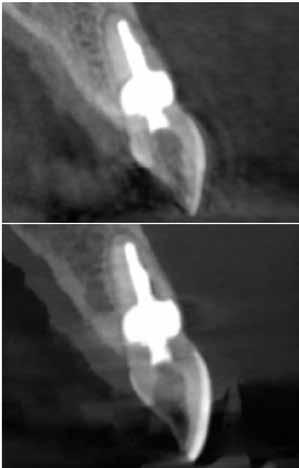

3. ábra: A gyökértömés elkészítése során készített felvétel.

4. a–b. ábra: A reszorbciós üreg Biodentine-nel való feltöltése. Intraoperatív (a) és radiológiai felvétel (b). – 5. ábra: Az öt hónappal később látható állapot. Nem észlelhetők gyulladás fennállására utaló jelek.

A kezelés befejezését követően 30 hónappal készített CBCT-felvételen a gyógyulás jelei észlelhetők.

A gyökértömés elkészítése során meleg vertikális kompakciós technikát alkalmaztunk, sealerként pedig CeraSeal-t (Meta Biomed; 3. ábra) használtunk. A reszorbciós üreget Biodentine-nel (Septodont; 4. a–b ábra) töltöttük fel. A reszorbcióval érintett területtől koronális irányba elhelyezkedő csatornaszakaszt pedig tisztán meleg guttaperchával kezeltük. Ezt követően a lebenyszéleket visszafektettük, és varratok behelyezésével eredeti pozíciójuknak megfelelően rögzítettük. A koronai részt kompozit tömőanyag segítségével állítottuk helyre. Kontrollvizsgálatra 5, illetve 30 hónappal később került sor (5. ábra). A csontos telődés jelei már 5 hónap után észlelhetők voltak (6. a–c ábra). A 30 hónappal később végzett kontroll során sem találtunk csontban lévő lézióra, törésre vagy egyéb pathológiás elváltozásra utaló jeleket (7. a–b ábra)